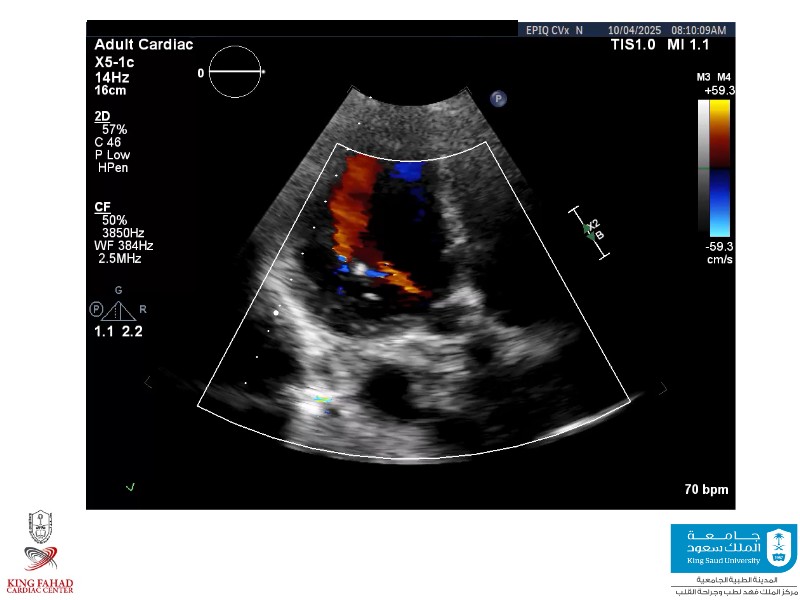

This session helps you anticipate and address complex scenarios such as mitral valve-in-valve, TAV-in-SAV, and valve-in-valve-in-valve procedures. Learn from expert case discussions that explore procedural strategies, technical challenges, and best practices to optimize outcomes in redo structural heart interventions.

- To anticipate and manage second valve scenarios with SAPIEN 3 Ultra RESILIA, including mitral valve-in-valve, TAV-in-SAV, and TAV-in-TAV

- To understand procedural strategies and challenges in complex redo scenarios using SAPIEN 3 Ultra RESILIA